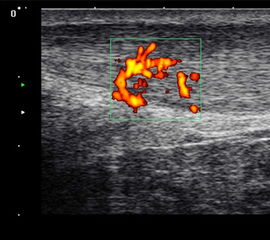

Die Farb-Doppler-Sonographie wurde 2001 erstmalig von Ohberg und Alfredson in Umea in Schweden bei schmerzhaften Achillessehnen eingesetzt 17. Bei 21 symptomatischen Sehnen konnten intratendionös mit Hilfe der Farb-Doppler-Sonographie pathologische Blutgefäße als Neovaskularisation nachgewiesen werden, die sich bei Achilles-gesunden Kontrollgruppe nicht fanden. Wenig später berichtete dieselbe Arbeitsgruppe über die erfolgreiche Farb-Doppler-kontrollierte Sklerosierung der Neogefäße mit Polidocanol 18.

2001 verglich Richards et al. die Power-Doppler-Sonographie bei symptomatischen Achillessehnenbeschwerden mit der Magnetresonanztomographie 19. Die Neogefäße in der Power-Doppler-Sonographie korrelierten mit Signalveränderungen in den T2-gewichteten MRT-Sequenzen. Aufgrund der guten Reproduzierbarkeit und Verfügbarkeit hat sich die Power-Doppler-Sonographie inzwischen bei der Darstellung der kleinen Neogefäße mit ihrem langsamen Blutfluss etabliert 202122. Die Neogefäße dringen von ventral in die Achillessehne ein. Typischerweise sind diese Neogefäße erst ab einem Sehnendurchmesser von >6,5mm nachweisbar. Bei erfolgreich behandelter Achillestendinopathie kann nach einem Jahr ein Rückgang der Anzahl der Neogefäße in der Power-Doppler-Sonographie, eine Durchmesserreduktion sowie eine Normalisierung der MRT-Signalalteration beobachtet werden 23. In einer Fallstudie konnte ein Abfall des Neovaskularisationsvolumens bei einem Patienten mit mid-portion Achillestendinopathie von 463mm3 auf 117mm3 belegt werden 24. Dies ging mit einer Verbesserung des Schmerzes in der visuellen Analogskala (von 8 auf 0) und des VISA-Scores (von 2 auf 92) einher.

634 asymptomatische Marathonläufer wurden mit der hochauflösenden Power-Doppler-Sonographie (12MHz) anlässlich von 23 Marathonveranstaltungen und 6 und 12 Monate im Anschluss untersucht 25. Mit einer odds ratio von 6.9 (p<0,001) konnte eine Neovaskularisation bei asymptomatischen Läufern die Entwicklung einer midportion Achillestendinopathie anzeigen. Eine positive Vorgeschichte für Achillessehnenbeschwerden hatte eine odds ratio von 3,8 und stellt damit ebenfalls einen ernst zu nehmenden Risikofaktor für weitere Beschwerden dar.